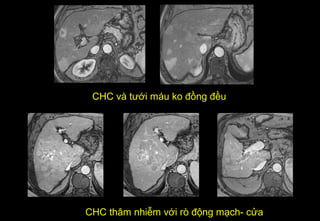

CHC và tưới máu ko đồng đều

CHC thâm nhiễm với rò động mạch- cửa